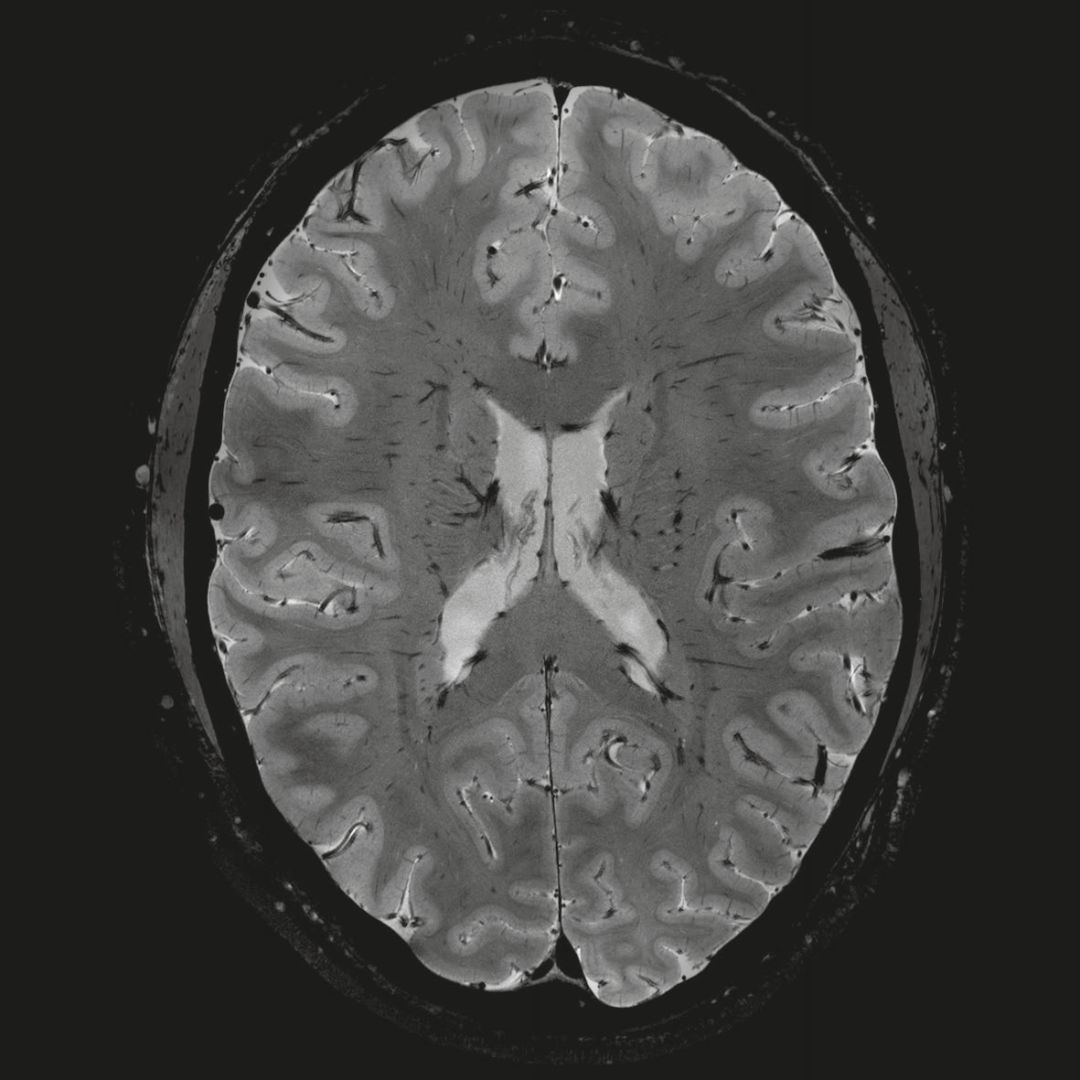

但近年來,西門子與科研機(jī)構(gòu)共同研究發(fā)現(xiàn),7T提供了數(shù)倍于傳統(tǒng)3T磁共振的信噪比和空間分辨率,在神經(jīng)、血管、腫瘤、骨關(guān)節(jié)等多個(gè)方面都會(huì)帶來全新的突破性進(jìn)展。尤其是在目前常規(guī)影像設(shè)備難以診斷的神經(jīng)退行性疾病如阿茲海默氏病、帕金森病等疾病的發(fā)病機(jī)理、早期診斷、治療方案確定以及治療效果評(píng)估上,有著極大的潛力。

1毫米的各向同性分辨率DTI:神經(jīng)纖維束的交叉細(xì)節(jié)顯示

0.8毫米的各向同性分辨率:精確劃分灰質(zhì)和白質(zhì)

0.8毫米的各向同性分辨率:超精細(xì)的解剖細(xì)節(jié),例:小腦的精細(xì)結(jié)構(gòu)

超精細(xì)的解剖細(xì)節(jié):T2對(duì)比

0.17 x 0.17 x 0.8毫米分辨率超高。

(TOF)300微米的各向同性分辨率顯示最小的血管